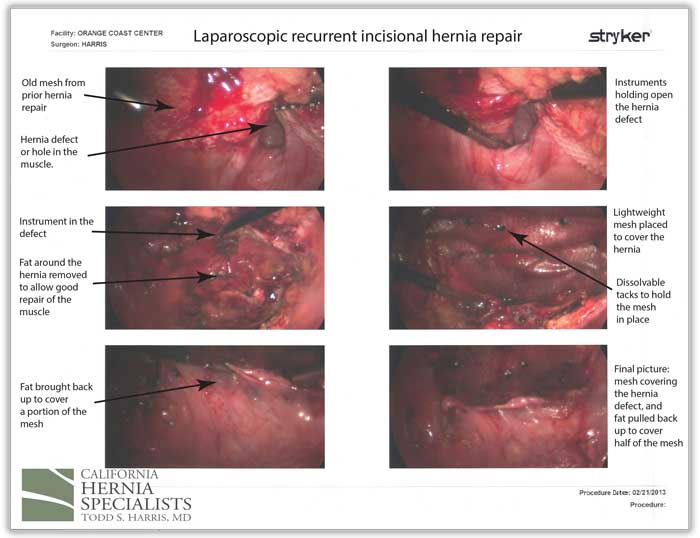

A 74 year old physician had a large pelvic tumor removed which was non cancerous. She developed a hernia 2 years after her surgery and underwent a laparoscopic incisional hernia repair at a large University Hospital in Southern California. Weeks after her surgery, she noticed a recurrent bulge in the lower part of her abdomen.

She presented to California Hernia Specialists for evaluation and treatment. On examination she had a 1-2 inch bulge in the lower abdomen, just above her pubic bone. This recurrent incisional hernia was painful when she exercised and while she was at work. We offered her laparoscopic recurrent incisional hernia repair.

The following video is a summary of her surgical procedure narrated by Dr. Harris.